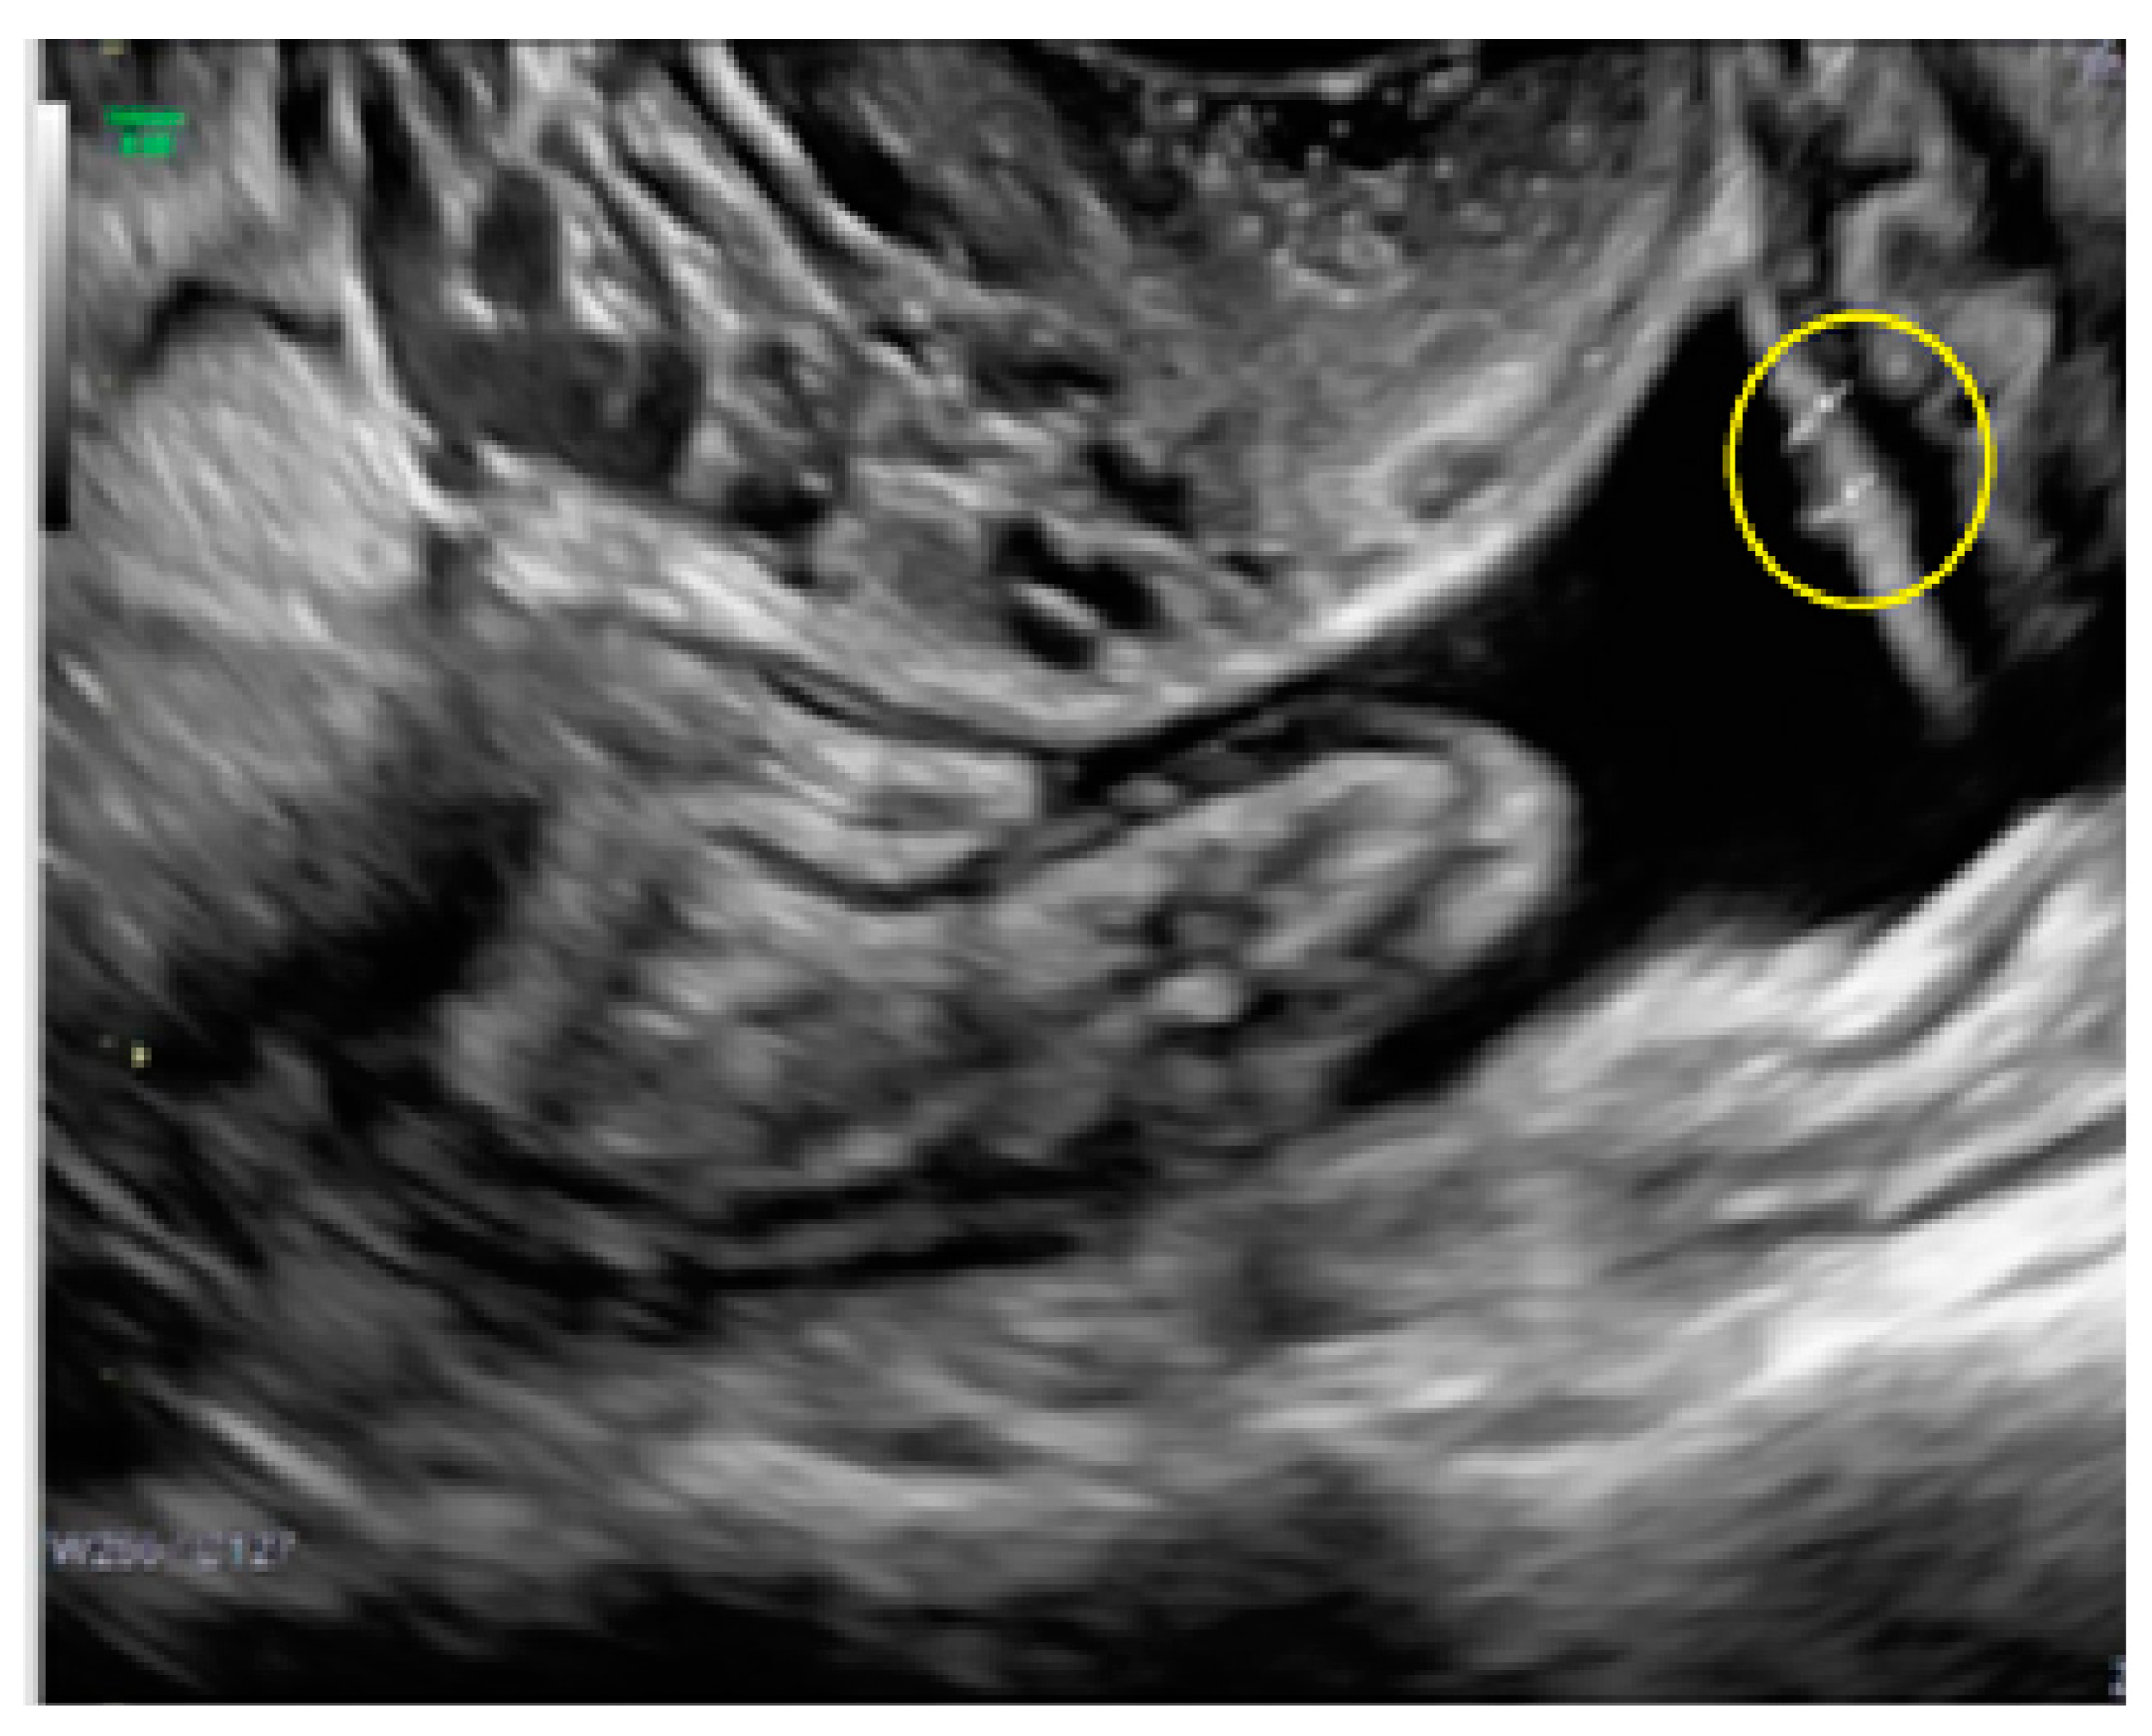

- The presence of velamentous (filmy) adhesions associated to the lesion (we called this a “veil”).